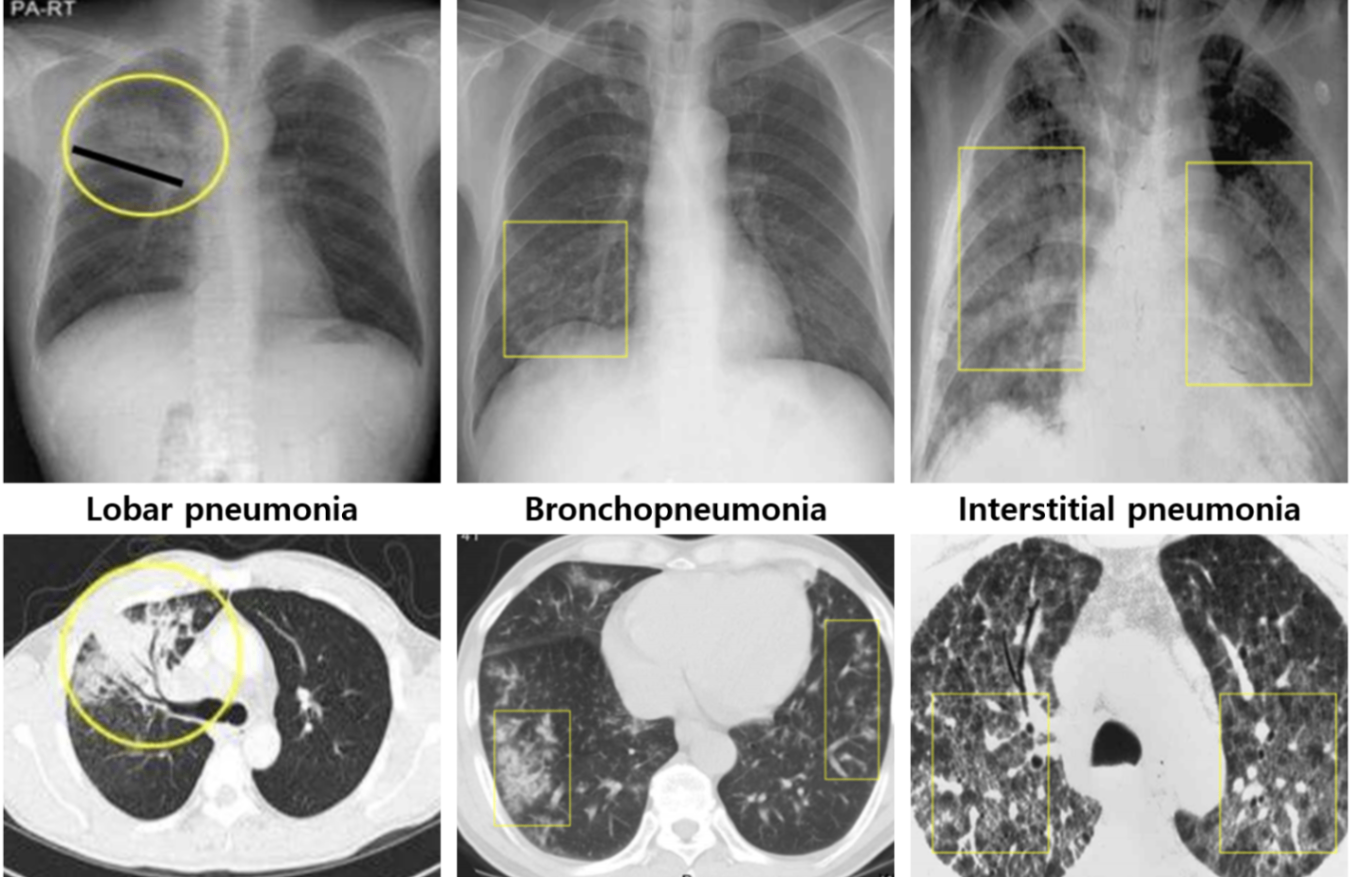

영상 소견에 따른 분류에 따라 대략적인 원인균을 추측할 수 있음 | ||

Lobar pneumonia (대엽성 폐렴) | Bronchopneumonia (기관지 폐렴) | Interstitial pneumonia (간질성 폐렴) |

Lobar consolidation | Peribronchial nodule | Ground-glass opacity(GGO) |

S. pneumoniae K. pneumoniae | Mycoplasma pneumoniae H. influenzae Virus | Pneumocystis jirovecii Mycoplasma pneumoniae Virus |

* 여기서 말하는 ‘interstitial pneumonia’는 간질성 폐질환(interstitial lung disease, ILD)에서 다루는 interstitial pneumonia와 다르다. 여기서의 ‘interstitial pneumonia’는 하나의 질환명이 아니라 폐렴에서 가능한 특정 영상학적 형태를 묘사하는 단어에 가깝다. 즉, 하나의 ‘진단명’으로서 간질성 폐렴이나 사이질 폐렴(interstitial pneumonia, interstitial pneumonitis)가 문제에 보기로서 주어질 때는 폐렴의 영상학적 분류를 이야기하는 것이 아닌 ILD를 말하는 것이므로 착오가 있어서는 안 된다.